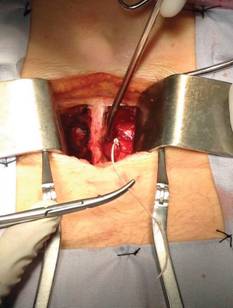

El procedimiento se realiza bajo anestesia general inhalada balanceada, posición decúbito ventral, teniendo como referencia catéter inhabilitado; se realiza incisión medial y mediante disección por planos se localiza catéter epidural en ligamento amarillo a nivel de L3-L4 procediendo a extracción del mismo confirmándose la presencia de nudo verdadero a aproximadamente 2-3 cm del extremo distal de catéter (Figuras 2, 3, 4 y 5). En transanestésico cursa sin eventualidades, cierre por planos, postquirúrgico sin eventualidades, pasa estable a piso de gineco-obstetricia.

Figura 3: Incisión por planos hasta llegar al sitio de anudamiento mediante abordaje a través de línea media lumbar.